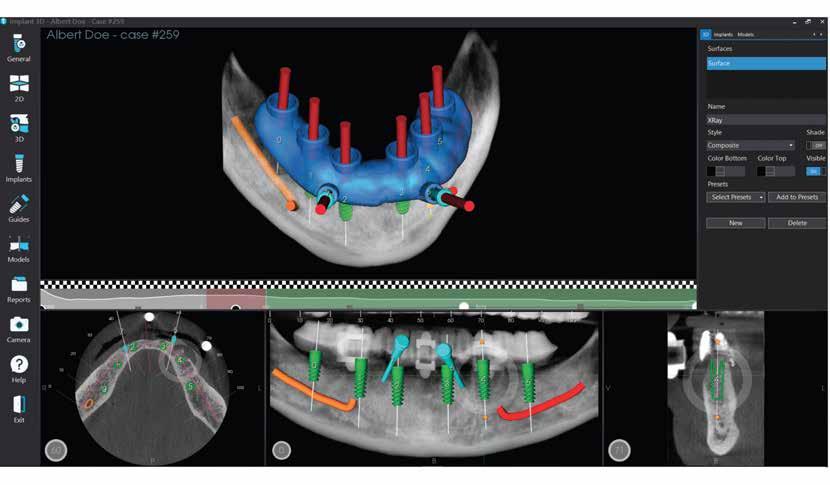

66 MediaLab: Implant 3D Guided Surgery Solutions